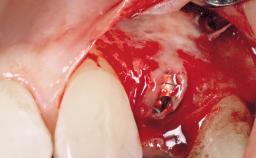

Placement Protocol Immediate implant placement

Socket Morphology Single-root socket

Socket Integrity Damage to one or more bone walls

Bone Volume Damage to one or more socket walls

Bone Augmentation Horizontal|Simultaneous

Augmentation Materials Xenogenous|Membrane

Soft Tissue Grafting Simultaneous